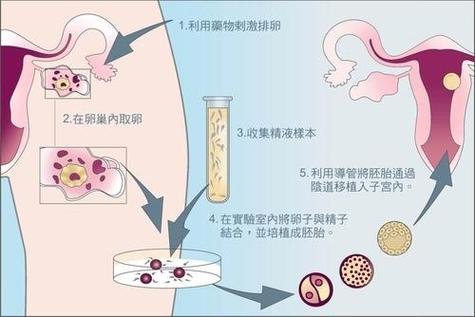

说起试管婴儿,很多人会想到“高科技”、“昂贵”等词,但很少有人会想到“失败”。然而,试管婴儿胚胎培养的失败是真实存在的,它给许多家庭带来了沉重的心理和经济负担。今天,我们就来谈谈试管婴儿胚胎培养失败的原因及其解决方案。

操作技术问题也不容忽视。据《生殖医学进展》2024年的数据显示,约有10%的试管婴儿失败是因为操作技术问题。包括胚胎移植技术、实验室培养环境等。

- 采用ICSI技术,提高受精率

- 引进先进的胚胎培养设备,提高实验室培养环境